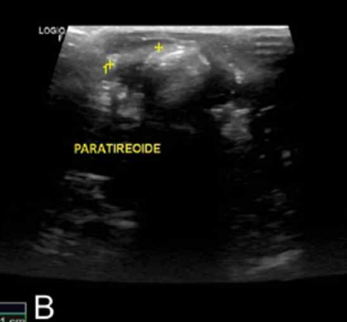

2) 진단

• 신체 검사

• 고양이에서 목의 혹이 잘 만져짐. → 갑기항이 압도적, 가끔 부갑기항

• 한 개 비대가 대부분. 2개 비대 : 10%, 3개 이상 거의 없음

• Percutaneous ultrasonography-guided ethanol ablation (with 96% ethanol)

• Percutaneous ultrasonography-guided radiofrequency heat ablation